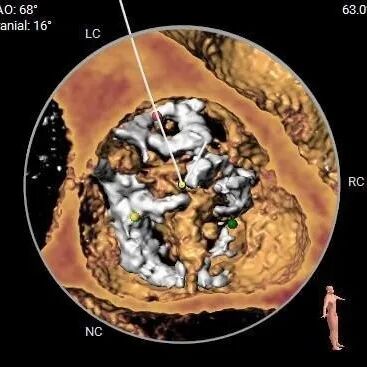

重度钙化,HU 850积分1192mm3

•功能型二叶瓣,瓣叶增厚,R-L间有钙化嵴,重度钙化,钙化于各窦内延伸分布,无冠窦内钙化居多,左、右冠窦下各有部分钙化向LVOT延伸;LVOT接近直筒型,

•左、右冠高度可,切线位测量,左窦瓣叶略长于左冠开口下缘;左主干分叉附近可见钙化分布,

•瓦氏窦增宽,STJ及升主扩张,

•主动脉瓣水平夹角约74°,严重横位心,主动脉弓宽度角度可,弓顶部有钙化分布,

•股-髂动脉走行稍迂曲,内径可,右侧股动脉穿刺点偏下位置有钙化块分布,腹主-髂总大量附壁钙化,

•推荐18mm球囊预扩,预装AV29瓣膜。